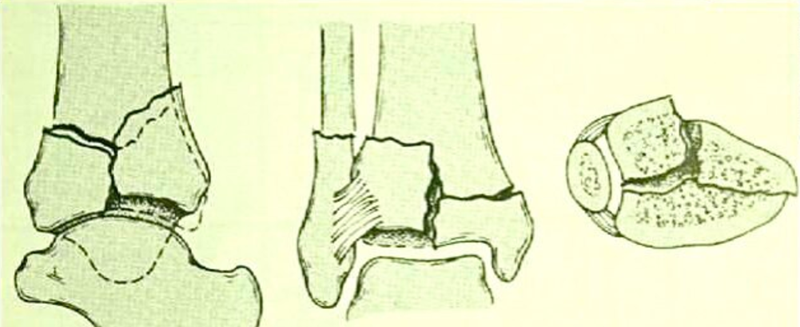

临床常以Ruedi-Allgower分型作为损伤分型。

图4 Ⅱ型:轻度嵌压或粉碎的移位骨折